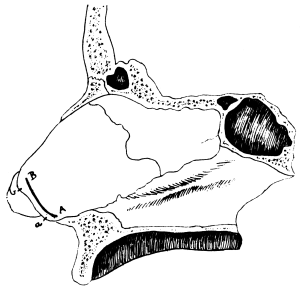

| 110. | The Normal Angle of the Anterior Chamber | 217 |

| 111. | The Angle of the Anterior Chamber from a Case of Recent Glaucoma | 218 |

| 112. | The Angle of the Chamber in a Case of Chronic Glaucoma | 219 |